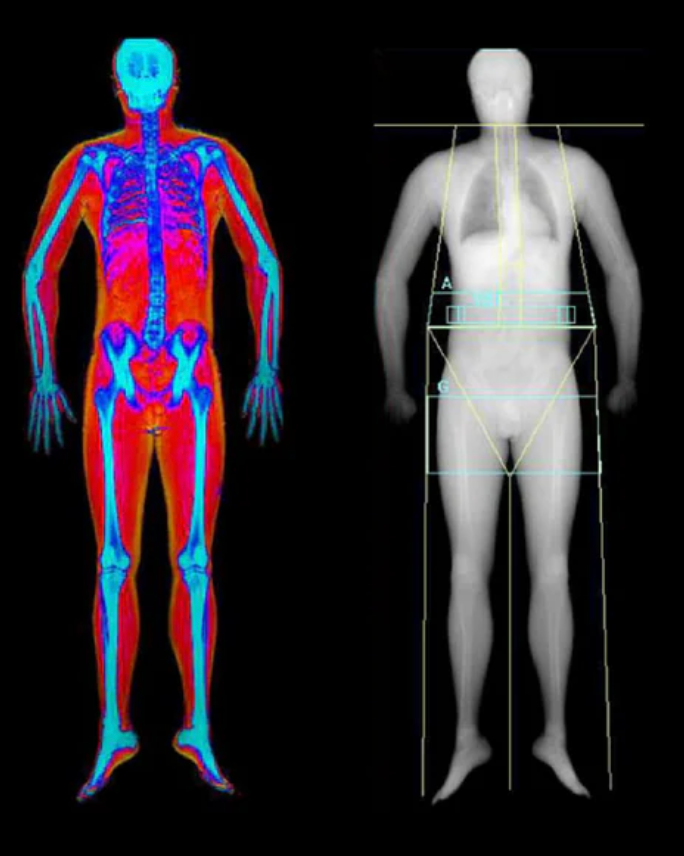

A DEXA scan (short for Dual-Energy X-ray Absorptiometry) is a simple, non-invasive scan that shows you exactly what your body is made of - fat, muscle, and bone.

Originally developed to measure bone density, DEXA has become the gold standard for body composition analysis. Unlike scales or BMI charts that only tell you how much you weigh, a DEXA scan breaks that weight down into real, meaningful data so you can understand your body on a deeper level.

Think of it as a full-body blueprint. In less than 10 minutes, you’ll get a precise, visual breakdown of your fat percentage, lean muscle mass, visceral fat (the fat stored around your organs), and bone density.